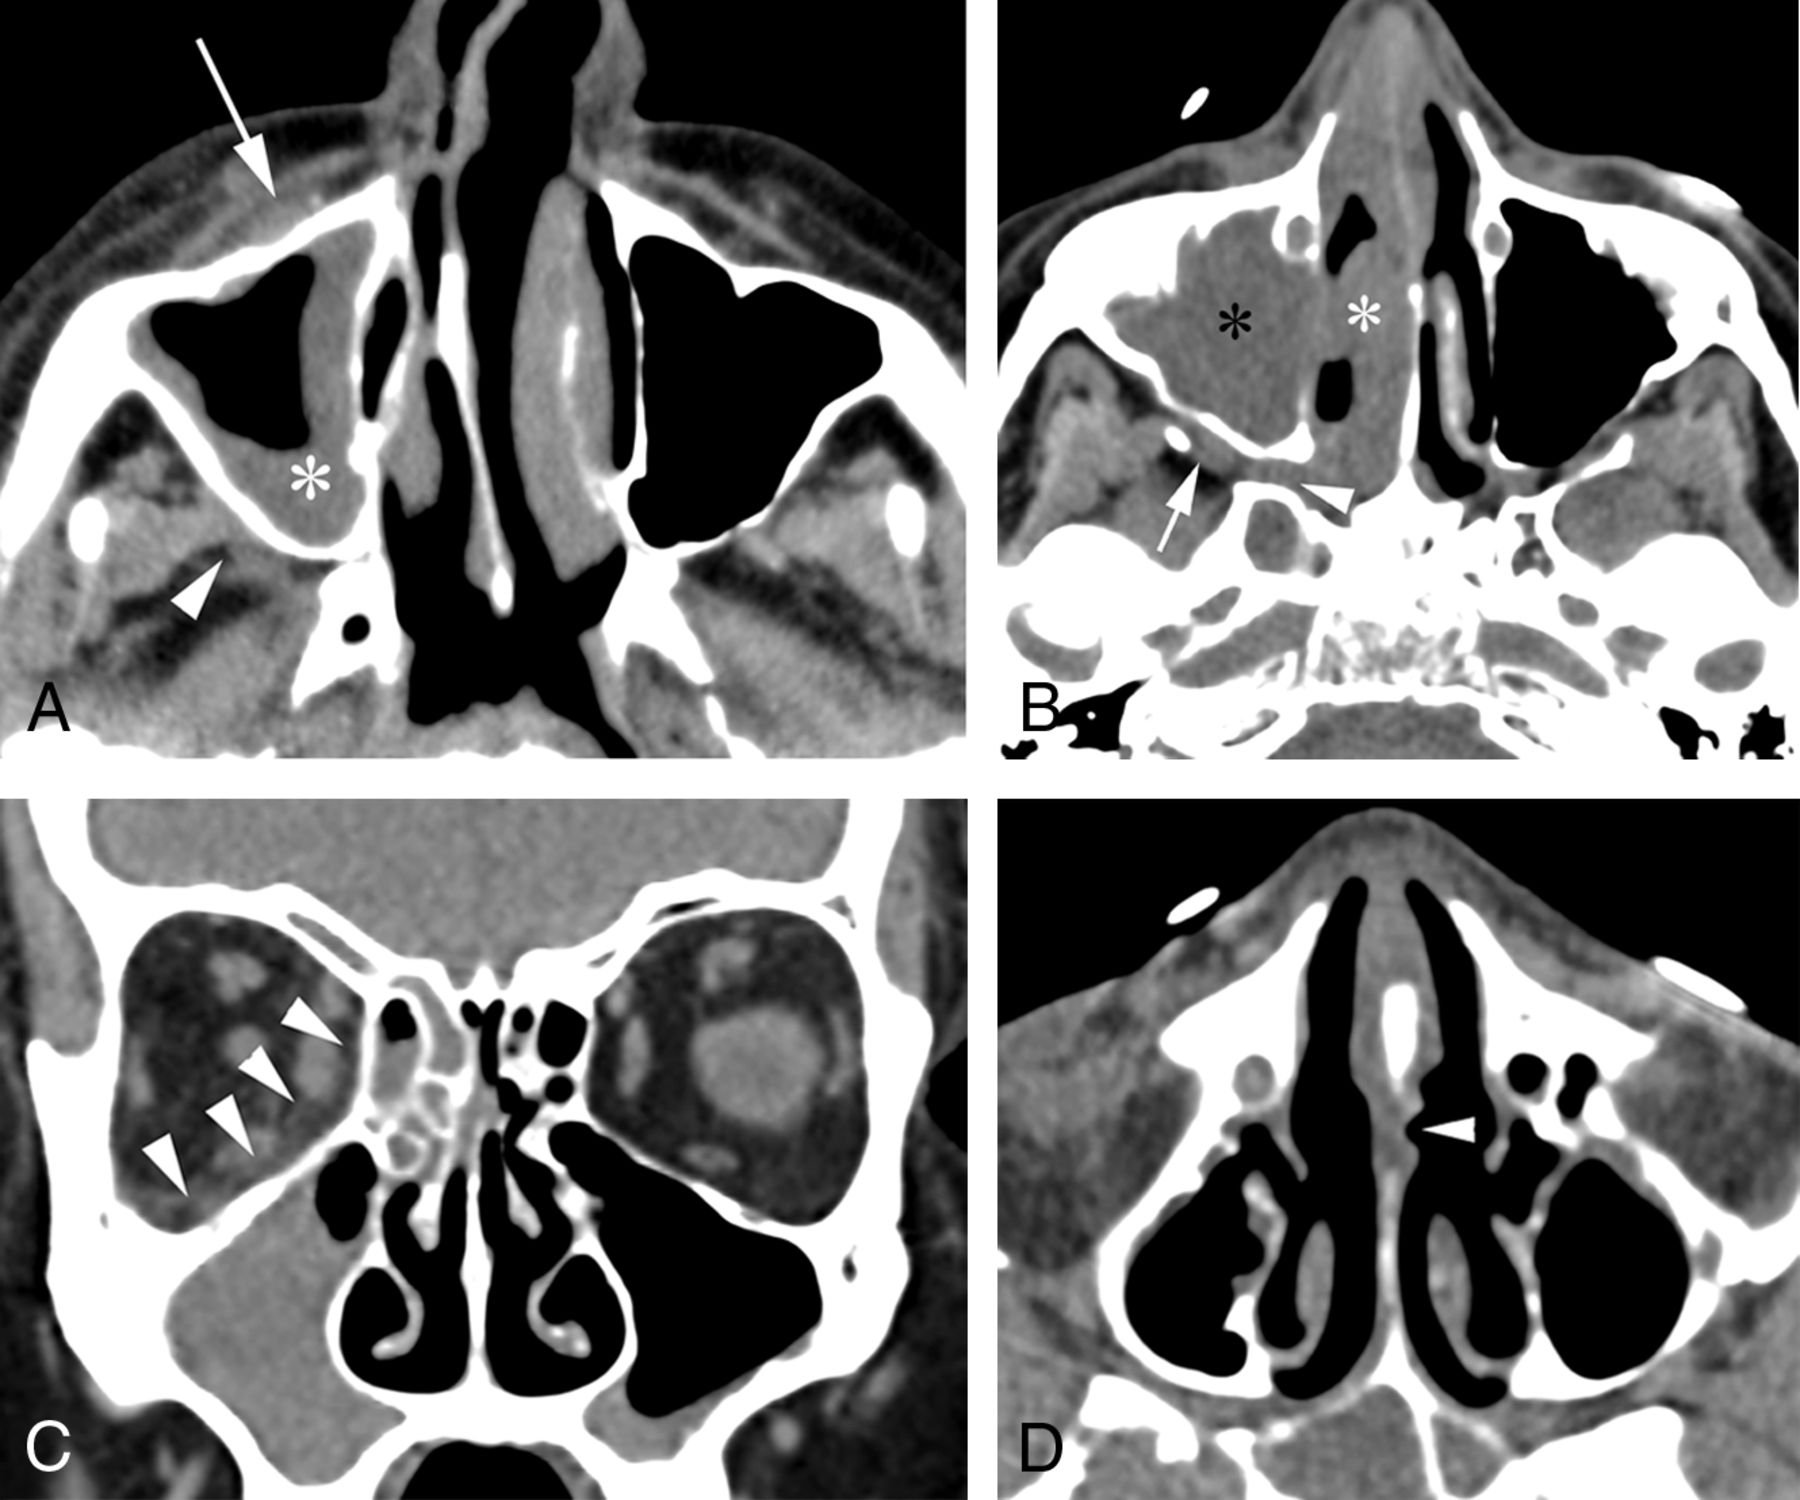

Thirteen variables had 100% specificity for AIFR, but only 5 of these had a sensitivity of >30% (nasolacrimal duct, lacrimal sac, septal ulceration, orbital involvement, and bone dehiscence; Figs 2 and 3). The remaining variables with 100% specificity represented late-stage disease findings (epidural, subdural, abscess, venous thrombosis, arterial thrombosis, cavernous sinus involvement, intraparenchymal extension, and horizontal palate involvement; Fig 4). Variables related to the degree of opacity had relatively poor sensitivity and specificity as binary variables.

Examples of established findings in AIFR. A, Axial CT image shows unilateral mucosal thickening involving the right maxillary sinus (asterisk) with soft-tissue infiltration of the right anterior periantral fat (arrow) and the posterior periantral fat (arrowhead). B, Axial image in a different patient shows unilateral right nasal cavity (white asterisk) and maxillary sinus (black asterisk) mucosal thickening. Soft-tissue infiltration through the right sphenopalatine foramen and pterygopalatine fossa (arrowhead) is seen, as well as involvement of the right posterior periantral fat (arrow). C, Coronal CT in a third patient illustrates orbital involvement of AIFR with subtle infiltration of the right medial and inferior extraconal orbital fat (arrowheads), despite the absence of bone erosion. D, Axial CT shows a surgically proved subtle ulceration along the left side of the nasal septum (arrowhead) in a fourth patient.